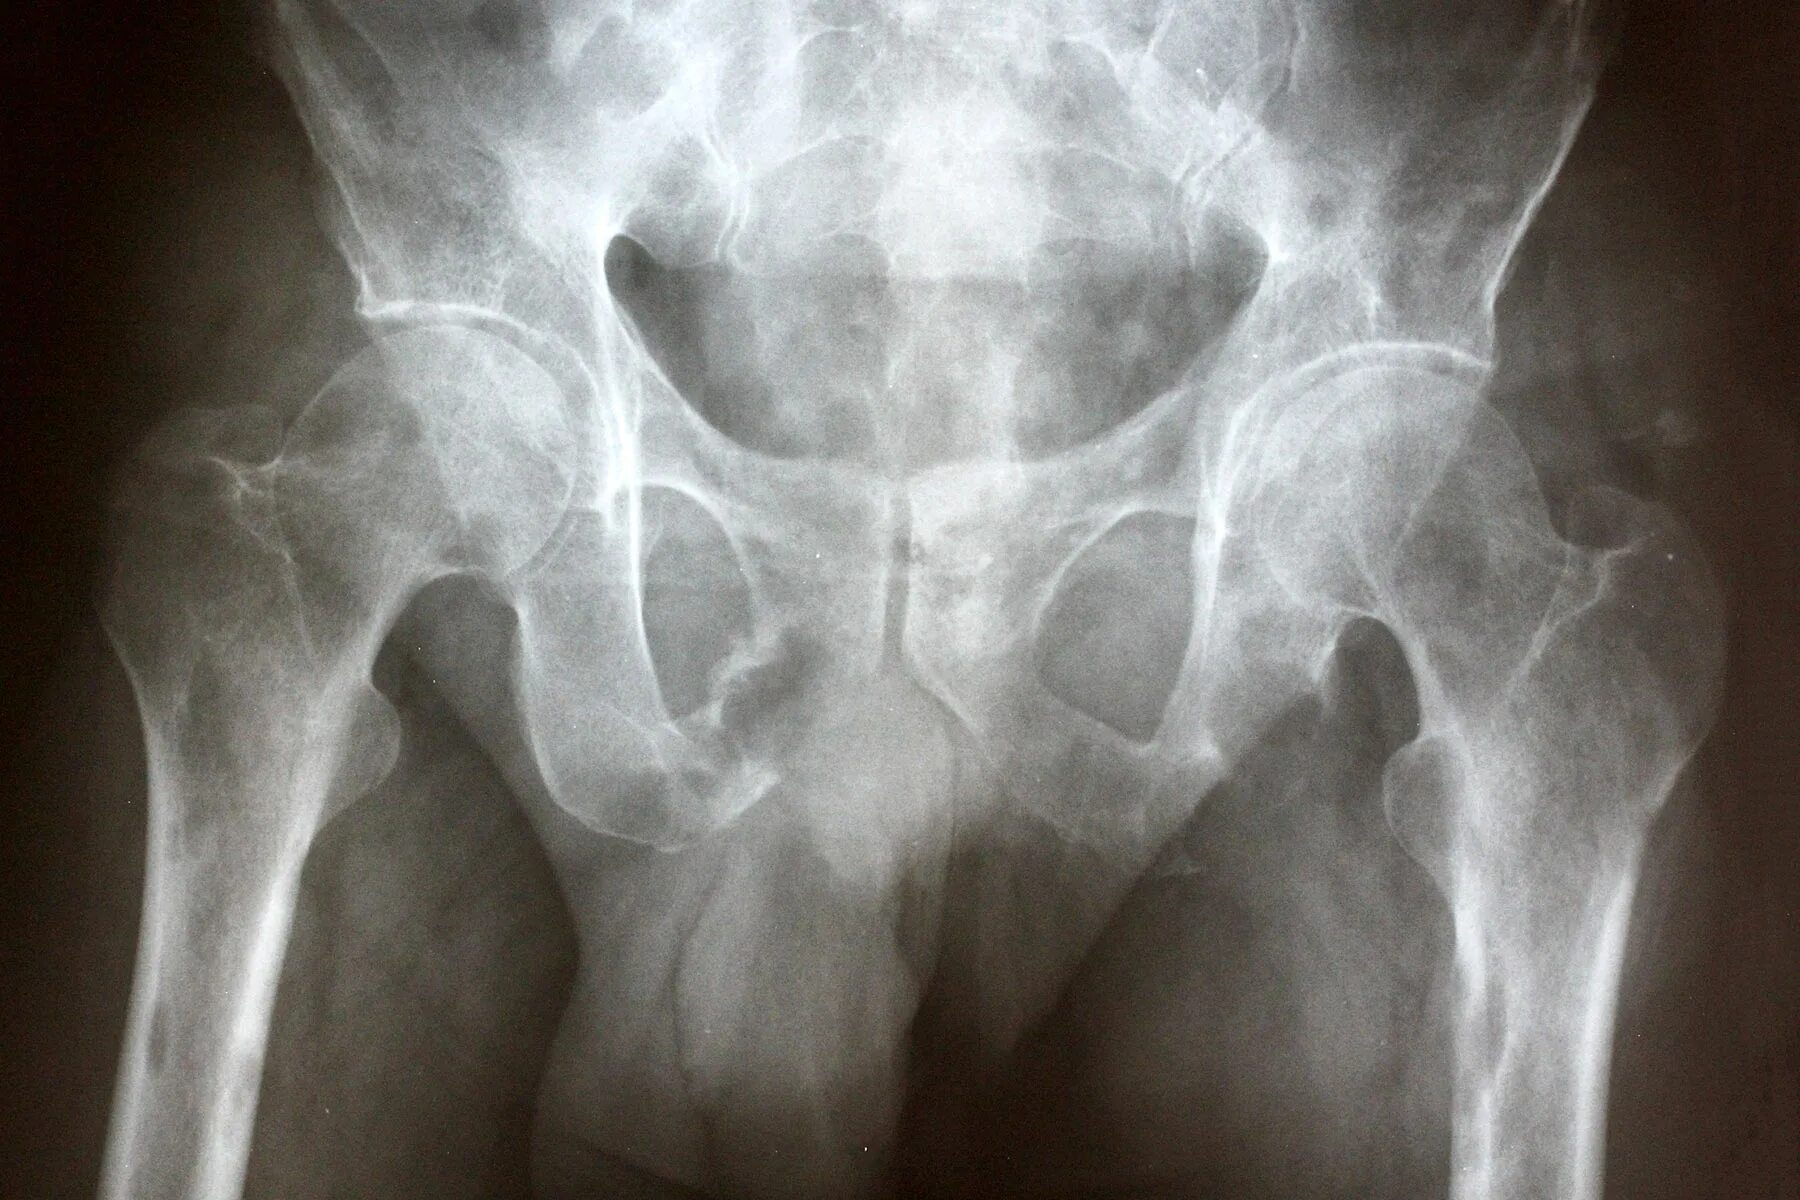

Метастазы в тазу